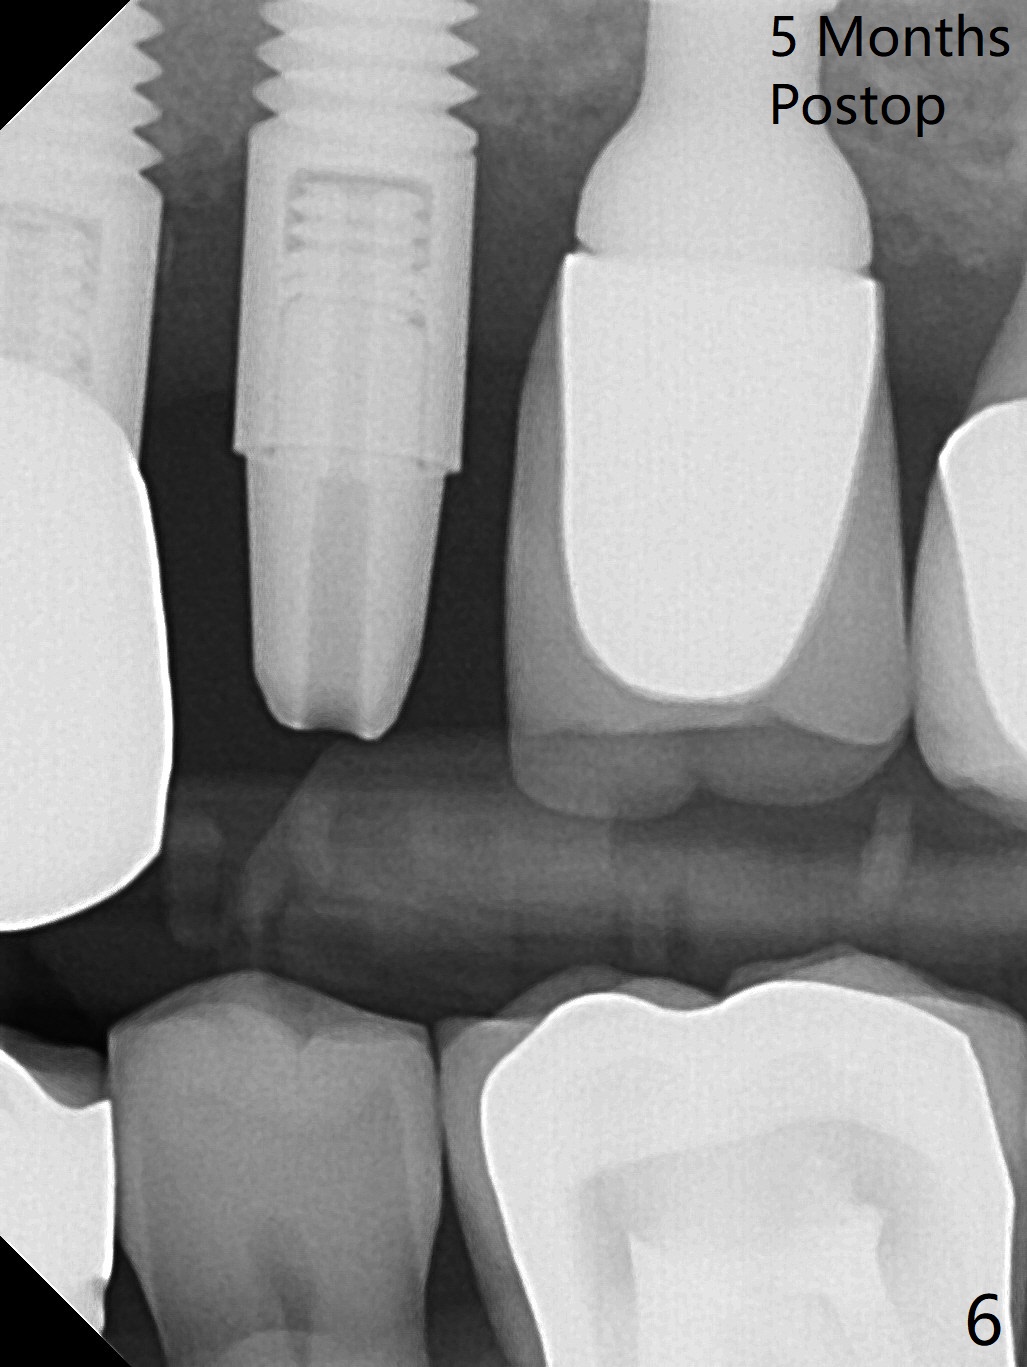

The root of the tooth #13 has an oblique fracture as related to a prefabricated post after 9 years of service (Fig.1). The trajectory of the initial osteotomy (Fig.2) is corrected with Lindamann bur and reuse of 2 mm drill (Fig.3). A 4x20 mm tissue-level implant is placed with > 60 Ncm, followed by tightening a 3.5x5 mm abutment (Fig.4,5); the mesiobuccal defect being filled with Vera Graft (Fig.4 *). An immediate provisional is fabricated. It appears that the implant should have been placed deeper (Fig.6: 5 months postop).